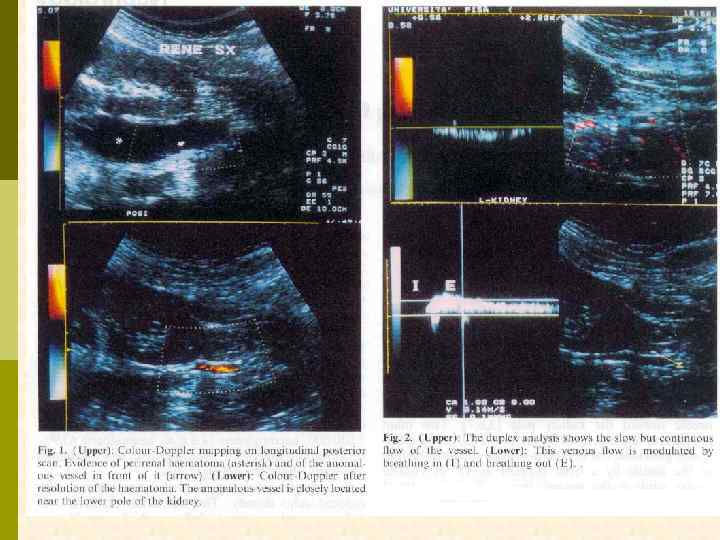

ВАРИАНТЫ УСТАНОВЛЕНИЯ МЕСТА РАСПОЛОЖЕНИЯ ПОЧКИ А. Обзорный снимок почки Б. Внутривенная урография В. УЗИ (допплер? ) Г. Геометрическая проекция

УЛЬТРАЗВУКОВОЕ ИССЛЕДОВАНИЕ ПЕРЕД ВЫПОЛНЕНИЕМ НЕФРОБИОПСИИ

ЛОКАЛИЗАЦИЯ БИОПСИОННОЙ ИГЛЫ ПРИ УЛЬТРАЗВУКОВОМ ИССЛЕДОВАНИИ

ВОЗМОЖНЫЕ ОСЛОЖНЕНИЯ ДИАГНОСТИЧЕСКОЙ НЕФРОБИОПСИИ p p p p В ходе выполнения биопсии – коллапс, психоз и пр. ) Паранефральная или субкапсулярная гематома (ранняя или поздняя) Макрогематурия Артерио-венозная фистула Разрыв почки Повреждение близлежащих органов Летальный исход